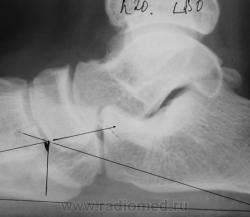

Первичная постановка на военный учет. Направлен из военкомата для определения наличия продольного плоскостопия и наличия/отсутствия деформирующего артроза в суставах среднего отдела стопы. Данные рентгенометрии свидетельствуют о наличии продольного плоскостопия 2-3 ст.

ОА т/л суставов 1ст. Слева выражена таранная шпора. У военных нет 2-3 степени. Либо 2, либо3.

О годности/не годности судить хирургам ВВК. Если есть 3 ст., то не годен. О таранных шпорах в Приказе ничего не видел.

Вы правы, но есть упоминание об "экзостозах"

Я уже высказывал свое отрицательное мнение по поводу артрозов у малолеток. Но наша профессия настолько точна ( первая после богословия), что, в принципе, в каждом суставе можно найти сужение (поди сравни его с тем, каким он был до сужения), субхондральный склероз (суставная впадина и так физиологически склерозирована, как отделить физ. склероз от приобретенного), разные заострения... Короче, при опр. финансовой поддержке, да еще по всей цепочке мед. комиссии можно написать при  норме  3 степень артроза. А вот насчет таранной шпоры? Мне такой термин не попадался. А в данном случае, мне кажется, это такая форма таранной кости, ведь в этой шпоре прослеживается нормальный костный рисунок. А какой бы мог быть костный рисунок в куске извести?